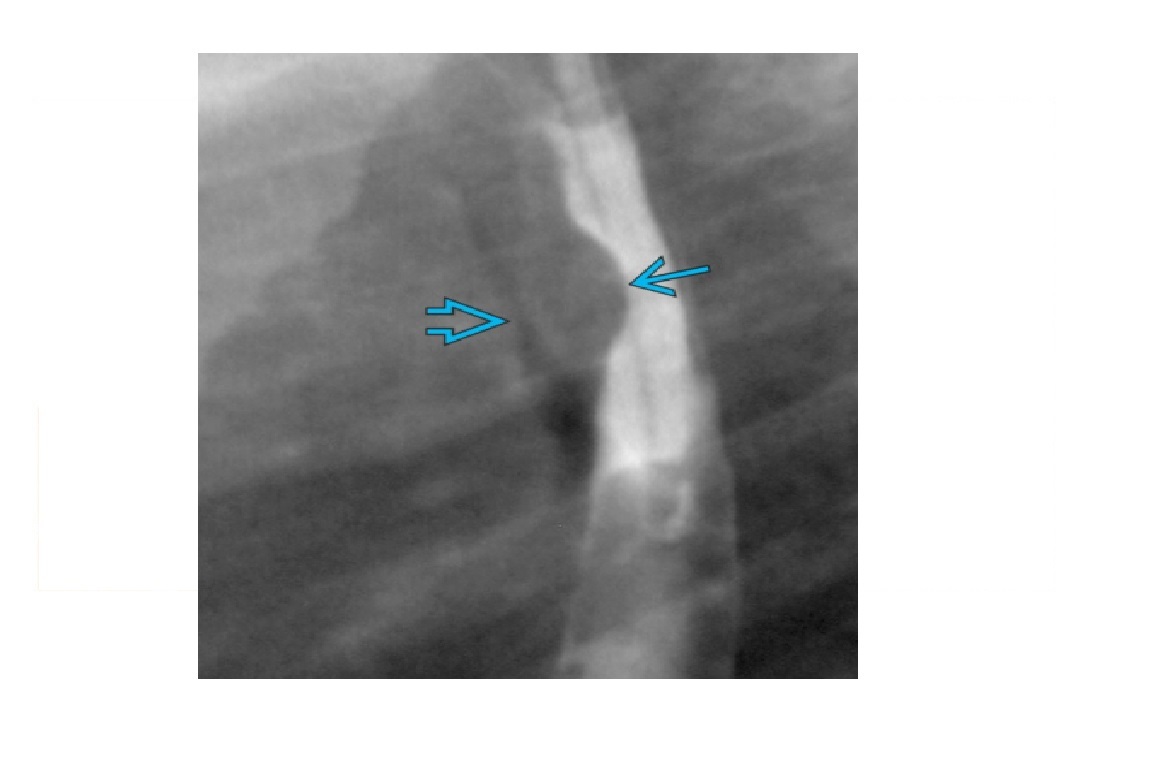

Eosinophilic oesophagitis

Barium - Concentric, ring-like strictures of oesophagus

**Not transient - Permanent **

DDx

feline oesophagus

- folds1-2 mm thick and run horizontally around the entire circumference of the esophageal lumen.

- The findings are transient, seen following reflux and not during swallowing.

- Associated with GORD

- distal two-thirds of the thoracic esophagus